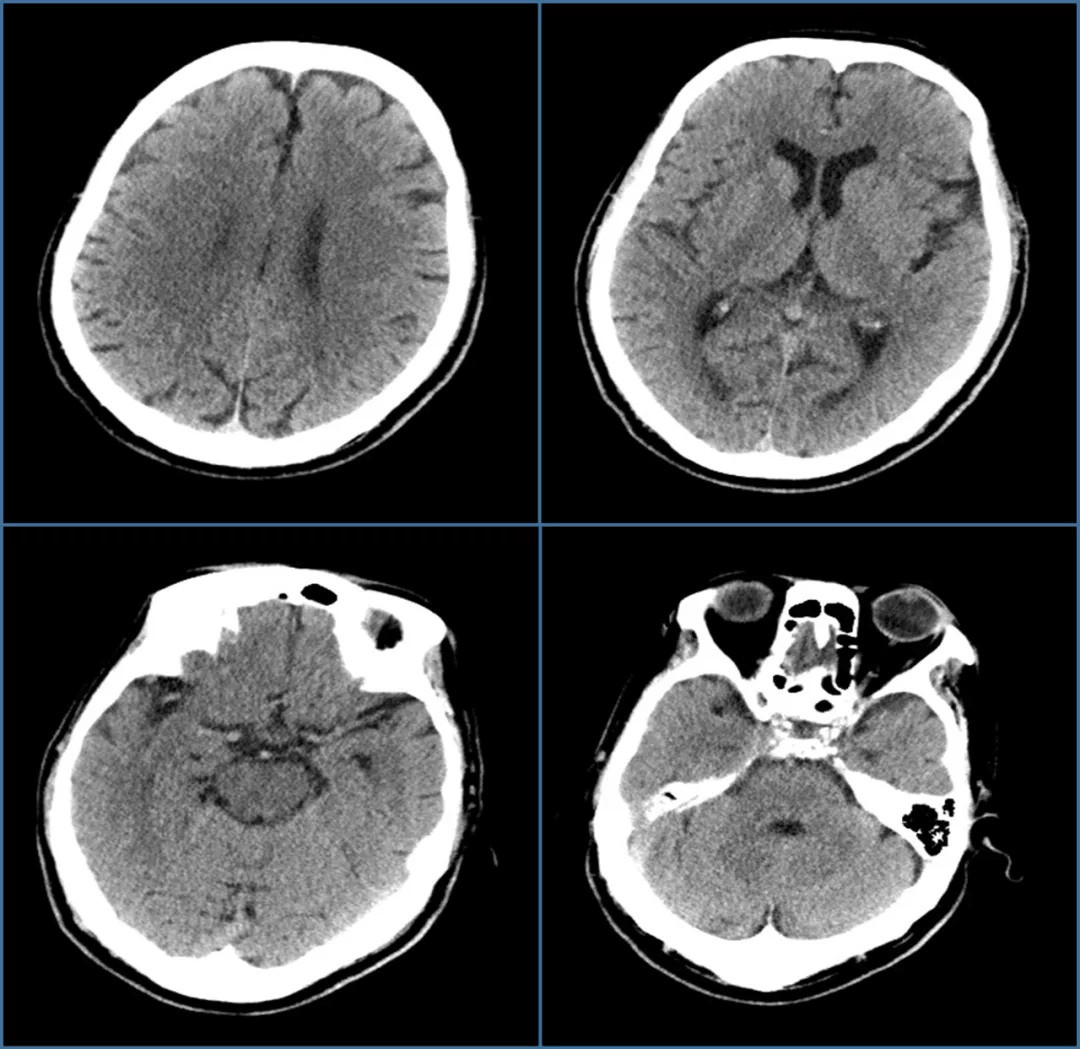

【识图断案】ct出现低密度的动脉管腔内充盈缺损,咋诊断?

图片尺寸512x512

肺动脉内的充盈缺损还有可能是这个病,你知道吗?

图片尺寸640x464